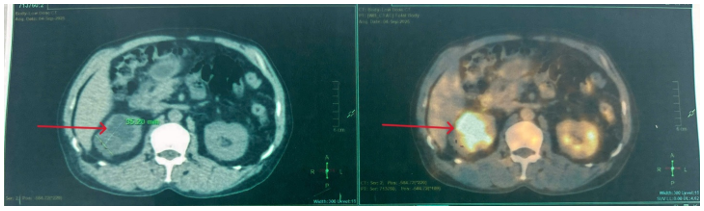

- Chụp CT bụng: Hình ảnh giãn đài bể thận và niệu quản phải do sỏi niệu quản đoạn 1/3 trên. Sỏi đài dưới thận phải.

Hình 2: Thận phải: Hình dạng và kích thước bình thường, nhu mô có nang 32mm. Đài bể thận giãn đường kính trước sau 15mm, đài dưới có sỏi kích thước 5mm. Niệu quản đoạn 1/3 trên giãn đường kính 9mm, có sỏi kích thước 7x13mm.

Hình 5: Hình ảnh đài – bể thận phải giãn độ II, còn sonde JJ niệu quản – bàng quang, nang thận phải đường kính 35mm